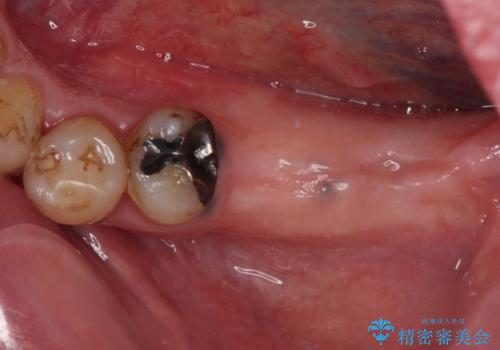

- 抜歯をしたものの、インプラントにするか入れ歯にするか悩んでいるうちに2年以上経過してしまったとのことで来院された患者様です。

自分の歯のように噛めるようにしたいとのことで、インプラントによる欠損補綴治療を行うこととしました。